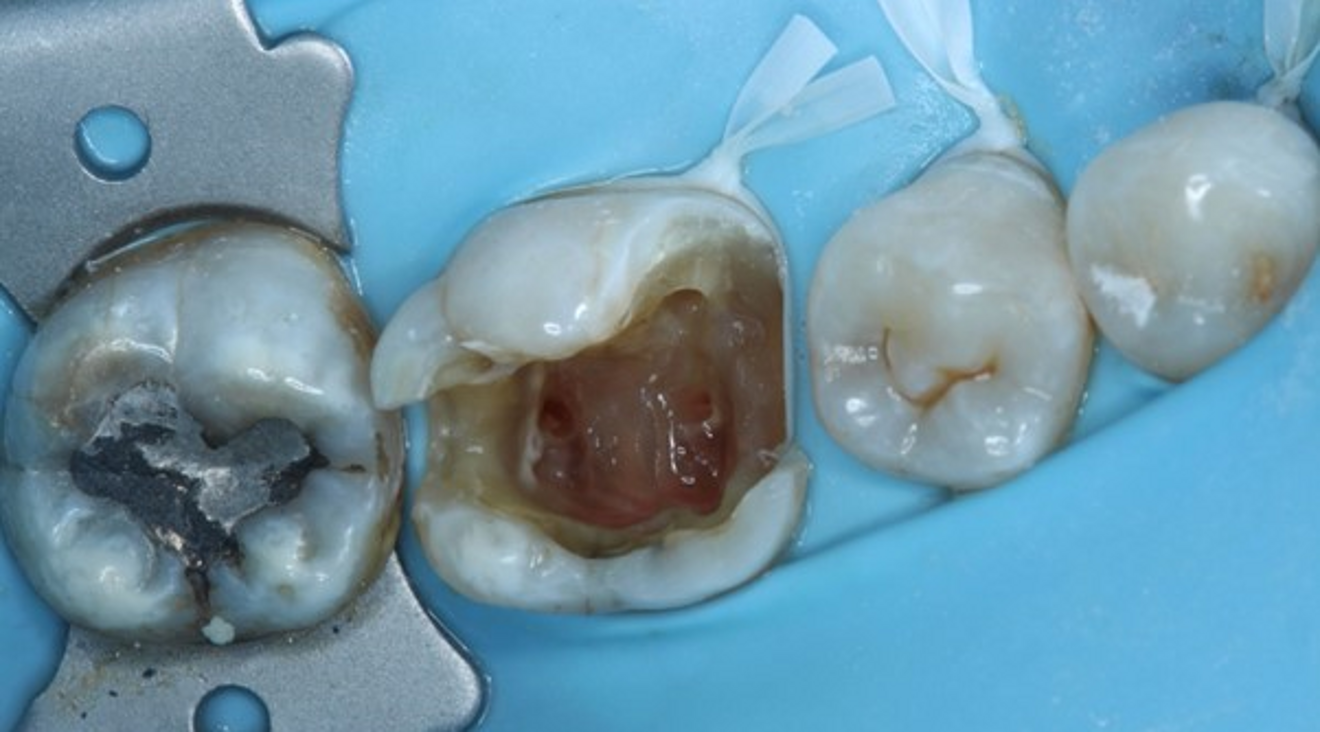

Extra-orally, no abnormality was detected. The intra-oral examination revealed an attempted extirpation; however, gross mesial caries had not been removed. The tooth mobility was Grade 0. The tooth was slightly tender to percussion, and there was mild buccal tenderness to palpation. There was no endodontic-related pocketing when the probe was walked around the gingival crevice. No evidence of a sinus tract or intra-oral swelling was found. A preoperative radiograph showed extensive mesial caries and a previous attempt at locating the canals. There was no obvious periapical pathosis radiographically (Fig. 1).

Local anaesthesia was administered with 4.4 ml of 2% lidocaine hydrochloride with 1:80,000 adrenaline via buccal infiltration and inferior dental nerve block. A dental dam was placed over teeth #37–34 using a HYGENIC Fiesta #7 clamp (COLTENE) and double floss ties to provide a tight seal (Fig. 2). The tooth was reassessed with caries removal having been carried out (Fig. 3), and four orifices located. The mesial cavity margin was deemed restorable; however, deep marginal elevation would be required. A decision was made to carry out the deep marginal elevation after cleaning and shaping of the root canal system to improve or maintain access to the root canal system.